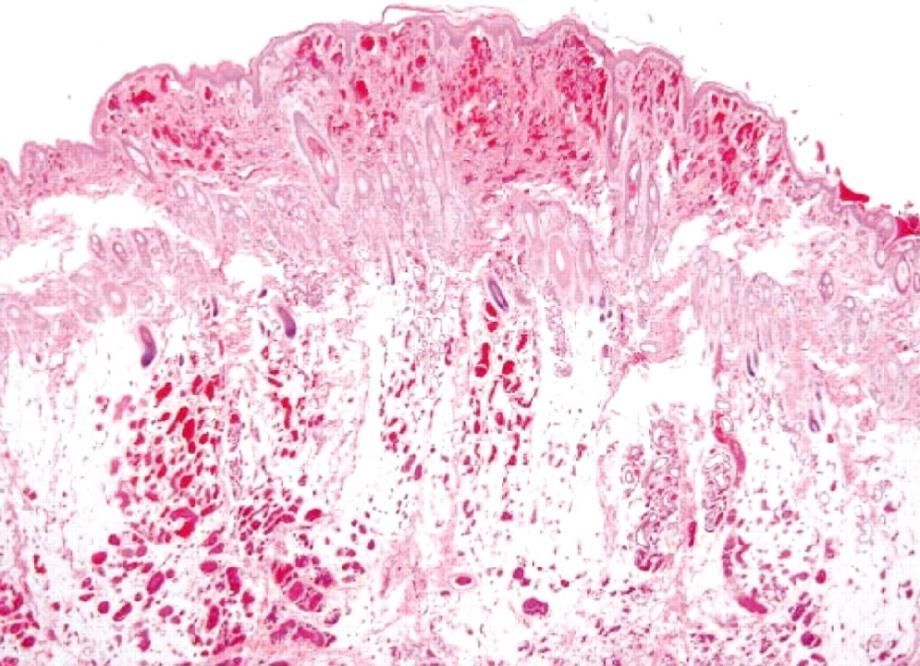

Lilly kommt aus einer deutschen Zucht zur neuen Besitzerin. Von Anfang an wird darauf hingewiesen, dass das Tier eine Geburtsgebrechen habe, welches schon abgeklärt worden sei: Eine Angiomatose am linken Vorderbein. Die neue Besitzerin legt uns den Befund einer Gewebeuntersuchung vor, welcher damals beim Welpen gemacht worden war - aufgrund dieser Hautbiopsie wurde die Diagnose der Gefässveränderung gestellt. Anlässlich der Kastration sehen wir die Hündin das erste Mal.

Anlässlich der Kastration werden in derselben Narkose mehrere Hautproben entnommen. Das Labor wird angewiesen, neben der normalen Untersuchung auch Spezialfärbungen zum Auffinden von speziellen Bakterien durchzuführen. Zur Diskussion der Resultate wird ein Dermatologe beigezogen.

Nach 10 Tagen werden die Fäden gezogen und die Untersuche besprochen: Das Labor bestätigt den Befund einer Angiomatose; es werden keine Bakterien aufgefunden. Da die Veränderungen gegenwärtig nicht zuzunehmen scheinen und der Hund symptomfrei ist, wird vorderhand abgewartet und keine Therapie eingeleitet.

Angiomatose ist ein Sammelbegriff für verschiedene, auf einer Vermehrung von Blutgefässgewebe basierenden Hautveränderungen. Die bei Hund und Katzen sehr selten auftretenden Veränderungen sind am häufigsten an den Beinen von jungen Tieren anzutreffen und können sich lokal infiltrativ ("einwachsend") verhalten und auch den unterliegenden Knochen schädigen. Es wird angenommen, dass es sich hierbei um eine Missbildung von Hautgefässen handelt, welche möglicherweise einen genetischen Hintergrund hat. Häufig breiten sich die Veränderungen mit der Zeit aus; die Therapie ist (falls möglich) eine chirurgische Entfernung. Es sind Fälle beschrieben, bei welchen im veränderten Gewebe spezielle Bakterien (Bartonella) gefunden wurden, welche möglicherweise die Ursache des Problem darstellen. Eine Spezialfärbung der Gewebeproben von Lilly zeigte allerdings keine Bartonellen.